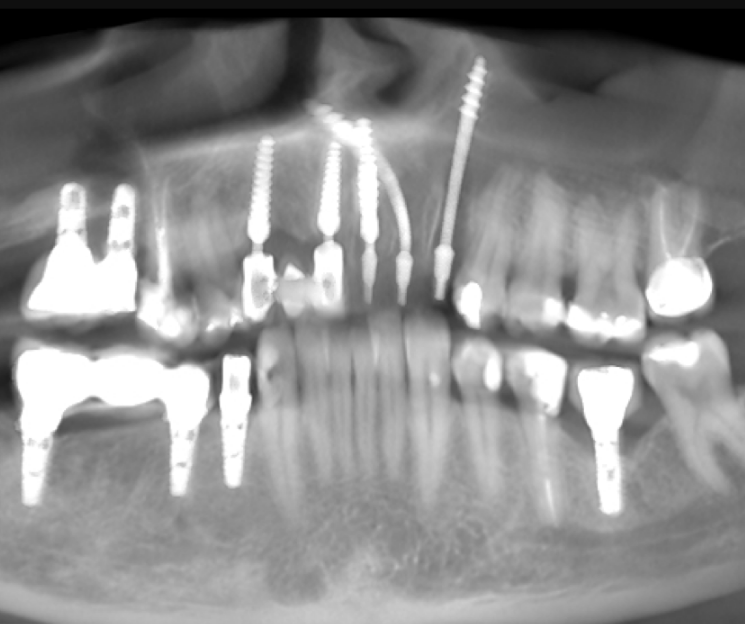

Extracción de piezas 21, 22 y 23 con infección activa

Paciente con infecciones de origen dental que comprometían severamente el hueso alveolar en la zona anterior superior. Se realizó la extracción de los dientes 21, 22 y 23, y se optó por una rehabilitación inmediata mediante implantes córticobasales.

Estrategia protésica e implantes utilizados:

- 1 implante córticobasal compresivo

- 2 implantes córticobasales rectos y finos

Esta combinación permitió anclar los implantes en hueso cortical, que mantiene su estabilidad incluso en presencia de procesos infecciosos en el hueso alveolar. El resultado: rehabilitación funcional y estética el mismo día de la cirugía.

La rehabilitación postextracción de los dientes 21, 22 y 23 con implantes córticobasales no es un caso aislado. Es un ejemplo claro de cómo la odontología moderna puede resolver situaciones complejas de forma inmediata, estética y funcional.